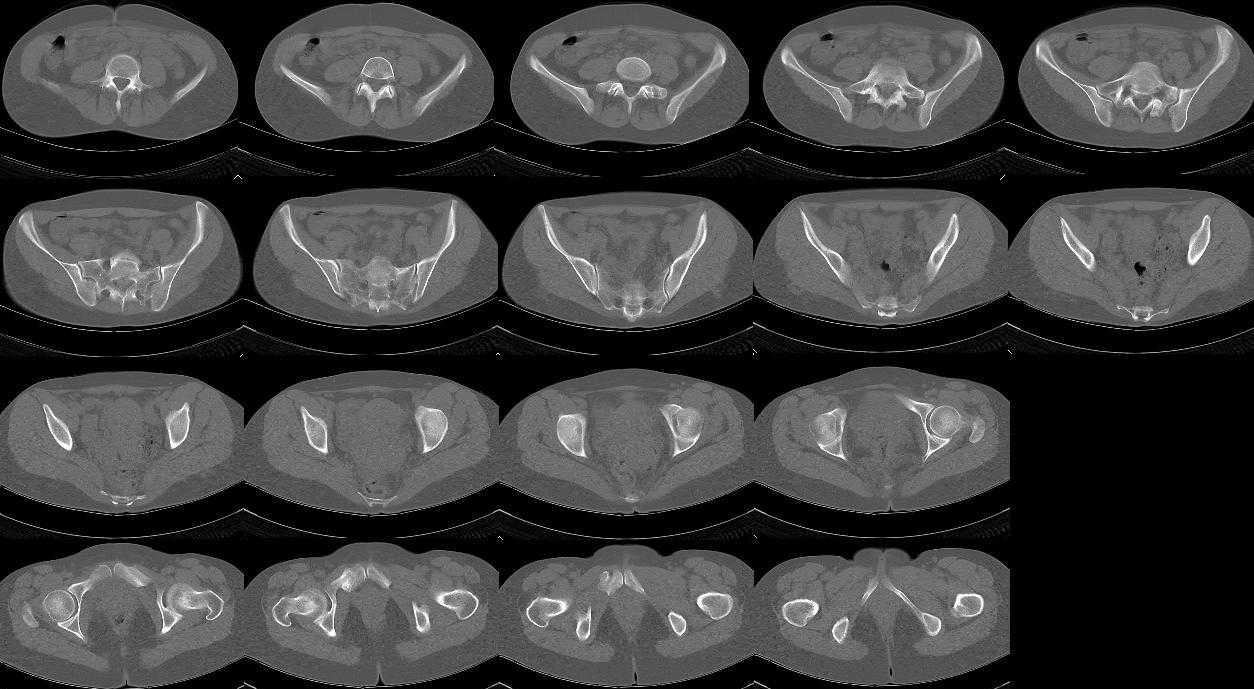

просьбе. досылаю КТ, фуккциональные Р-граммы пояснично-крестцового отдела позвоночника, фото пациентки.

Уважаемый Алексей. Описанные Вами клинические проявления указывают на нестабильность левого крестцово-подвздошного сочленения. Такие больные встречаются не редко (за последние 6мес.в нашей клинике оперировано 3 больных со сроками давности от 6мес. до 1 года). К сожалению рентгенологически их трудно обьективизировать. На КТ это проявляется артрозом и костными разрастаниями КПС. В Вашем случае рентгенограммы и представленные томограммы ничего не дали. Можно попробовать посмотреть связочный аппарат КПС на МРТ хотя не уверен что Вы получите окончательный ответ. Если Вы будете убеждены в этом диагнозе то выход один костно-пластический артродез левого крестцово-подвздошного сочленения с фиксацией канюлированными шурупами. Заманчиво конечно и устранить ротационное смещение половины таза, но это на Ваше усмотрение.

почему она должна возникнуть? Сломан вроде крестец, хотелось бы посмотреть функциональные снимки таза.